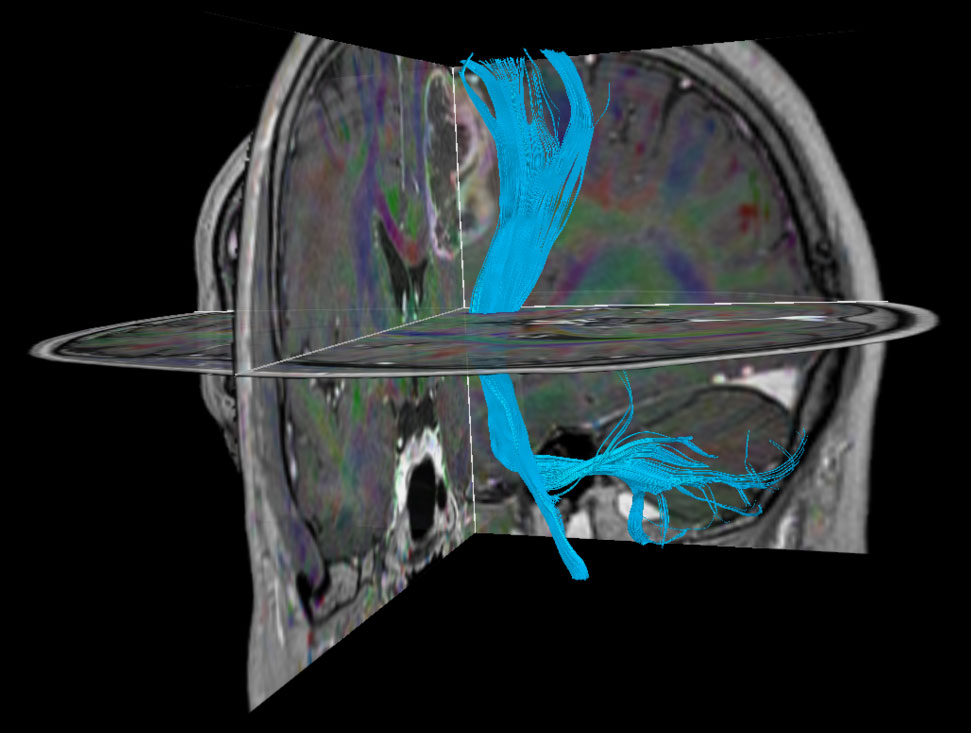

Patient with a revasculerized area with small bleedings. Diagnosed as malignant glioblastoom.

DTI FiberTrak